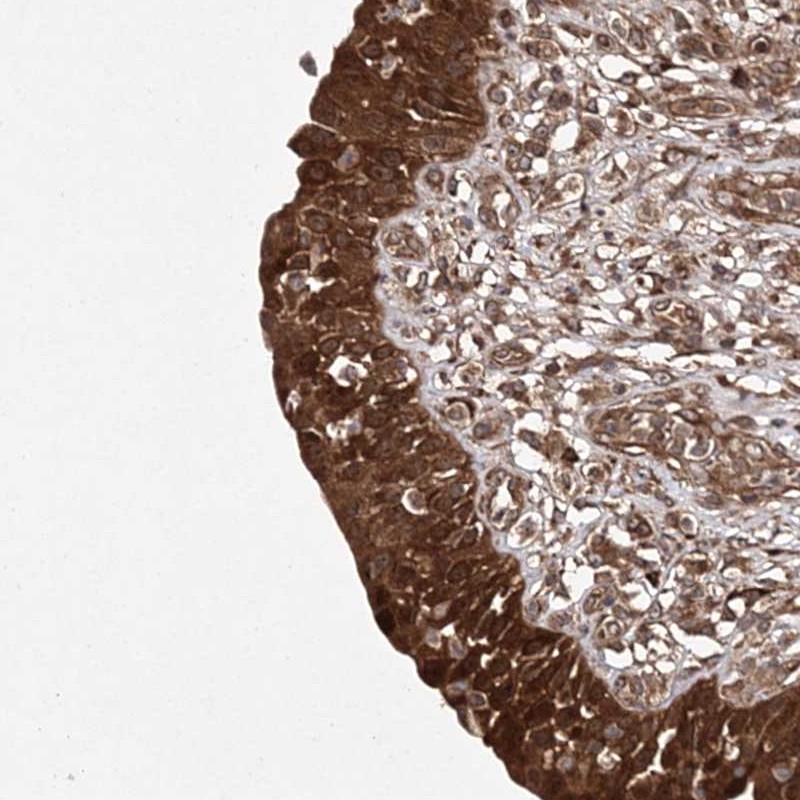

Immunohistochemical staining of human urinary bladder shows strong cytoplasmic positivity in urothelial cells.